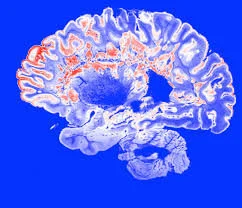

Multiple sclerosis (MS) is an autoimmune disease of the central nervous system that damages the myelin which is the covering layer of the white matter of neurons. Multiple sclerosis can affect parts of the brain, optic nerves and spinal cord. The result is disruption of the flow of information within the brain, and between the brain and body. When specific neurological pathways are affected, patients may develop weakness, stiffness, sensory loss, pain, incontinence, and visual problems. Many patients also complain of refractory fatigue and mood disturbances. A majority of MS patients experience “attacks” that mark the onset of new neurological deficits. MRI studies of the brain and/or spinal cord during these attacks will show new “spots” which are indicative of active damage to the central nervous system. Some of the new symptoms improve over time. However, if patients continue to accumulate new injuries, they will become progressively impaired over time and may become disabled. This can impact their ability to maintain employment and remain independent.

Doctors taking care of MS patients often use MRI studies to help determine if the disease is active or stable and how it is evolving over time. For example, the appearance of the visible spots may change over time and brain tissue can even diminish in volume over time. Patients are often prescribed medications that have been shown to decrease the number of new attacks. There is a subset of patients that do not get any new attacks over a long period of time and their disease is considered stable. These patients would not be expected to develop new symptoms related to their MS.